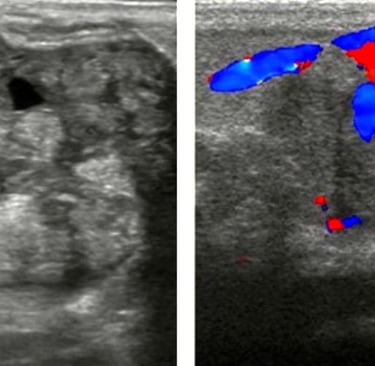

Hands-on sessions emphasize a systematic imaging protocol that covers normal tissue assessment, variant patterns, and subtle abnormalities. You’ll practice with focused coaching on image optimization, Doppler utilization, and documentation that supports meaningful clinical communication.